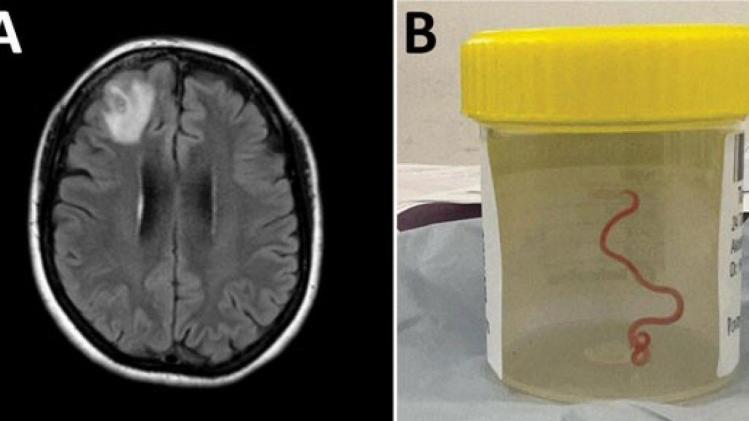

Les médecins ont découvert une «lésion atypique», grâce à un examen IRM, dans la partie frontale du cerveau de l’Australienne, âgée de 64 ans, qui souffrait de pertes de mémoire.

Il s’agissait d’un Ophidascaris robertsi, un ver rond de huit centimètres qui, selon les chercheurs, est un parasite des kangourous et des pythons, en Australie. Il parasite des animaux dans d’autres régions du monde, mais il n’avait encore jamais été détecté sur un être humain.

Le parasite, dont la «structure en forme de fil» est apparue sur les scanners cérébraux, a ensuite été identifié grâce à des tests ADN.